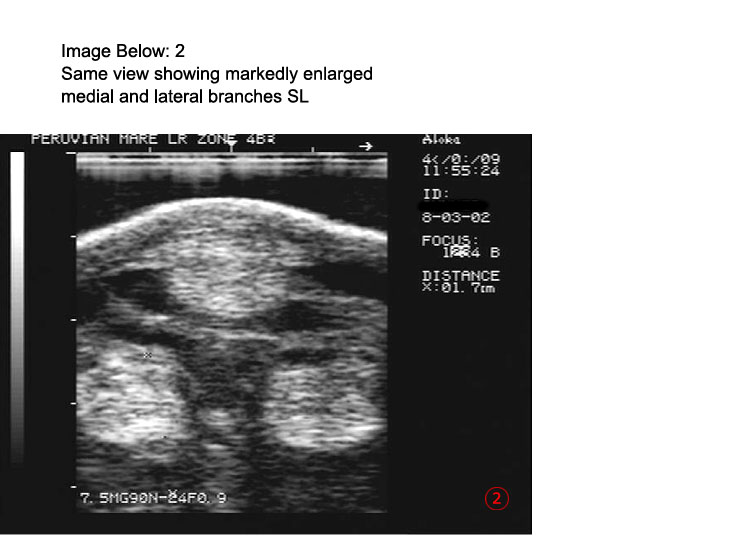

Ultrasound Images pg 2